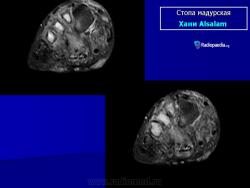

Заболевание прогрессирует как очаговые тканевые образования с формированием опухоли, участков нагноения и рубцов. Иногда формируется множество свищевых ходов, из которых выделяется гной с зернами. Инфекция никогда не распространяется гематогенно, однако может происходить распространение по лимфатическим путям - к региональным лимфатическим узлам и с последующим нагноением. Такие случаи требуют повторных хирургических вмешательств. Вовлеченные ткани могут также вторично загрязняться бактериями. Распространенность поражения мягких тканей лучше всего определять на магнитно-резонансной томографии (МРТ).

Рентгенологическую картину мадурской стопы мы считаем на основании изучения собственных 8 наблюдений и литературных данных чрезвычайно характерной, ничего общего не имеющей с картиной поражения стопы при всех других нозологических формах, в том числе и при актиномикозе. Один лишь взгляд на рентгенограмму достаточен, чтобы поставить диагноз заболевания, разумеется, при условии знакомства с этой болезнью (рис. 258). Эта картина слагается из наличия округлых кистовидных деструктивных очагов, более или менее густо пронизывающих как трубчатые, так и короткие кости стопы, как компактную, так и губчатую костную ткань. Остаются нормальными только фаланги и обычно дистальные концы плюсневых костей, если и не всех. Кости изъедены изнутри и снаружи, крайне истончены, суставные поверхности разъединены, между ними развиваются широкие диастазы. При всем этом глубоком разрушении скелета стопы ее костные элементы удивительным образом все же в основном сохраняют нормальные взаимоотношения, т. е. вся стопа как анатомо-функциональное целое не терпит никакого ущерба. Остеосклероз или периостальные реакции здесь бывают редко, если только нет осложнения остеомиелитом, а последний как раз никем достоверно при мицетоме стопы и не доказан. Об остеопорозе или атрофии костей, равно как об изменениях невротрофического характера в обычном смысле этих понятий, сказать что-нибудь определенное нет возможности, настолько глубоки изменения, которые претерпевает структура скелета стопы из-за основных деструктивных явлений.

Мицетома

Мицетома

Рисунок 21.21

Случаи и цифры